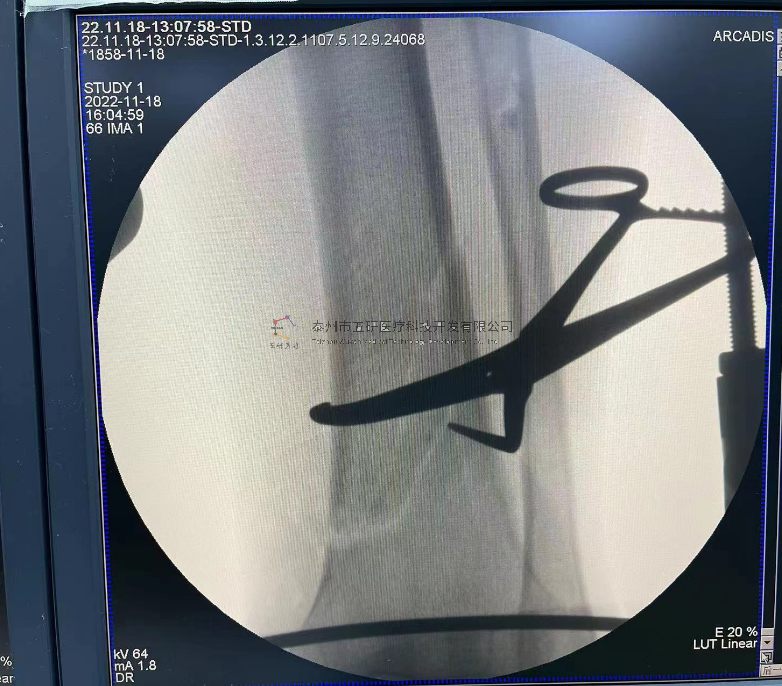

本病例由中國中醫(yī)科學院望京醫(yī)院骨綜科提供(術者:支架醫(yī)生常醫(yī)師)

【基本資料】患者,女,61歲

本病例腕架骨折。術前正側位片:右橈骨遠端骨折。

采用常規(guī)方法固定,自掌骨尺側,約基底稍偏遠處穿入螺紋針。